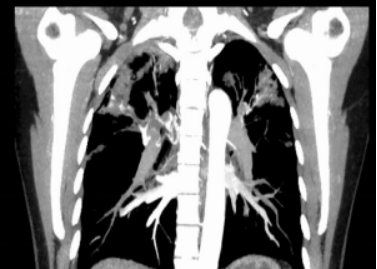

患者王公公,男,78岁,主因“咯血4+天,加重3+小时”于 2021-12-09入院。入院予以止血、对症等治疗。2021-12-09胸部CT、支气管动脉成像:右肺下叶后基底段结节影,考虑周围型肺癌可能性大;支气管动脉成像:右侧支气管动脉稍增粗。

2021-12-26行胸部CT、支气管动脉成像:

1、双肺炎变,右肺上叶空洞形成,考虑继发性肺结核伴空洞形成可能。

2、右肺上叶支气管扩张。

3、右肺上叶支气管动脉增迂曲;主动脉钙化。